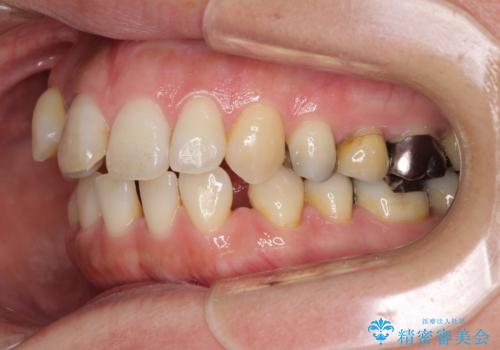

- 八重歯と前歯の隙間を気にして来院された患者様です。

下顎前歯は2本欠損しており、それが原因で隙間ができていました。

また、その影響で上下歯列がアンバランスとなっており、上下前が非接触となっていました。

上下のバランスを取って八重歯などを解消するため、上顎左右第1小臼歯を抜歯することとしました。

上顎左右第1小臼歯を抜歯したことで、隙間が閉じた下顎歯列の位置まで前歯を引っ込ますことができたため、口の閉じにくさを解消することができました。